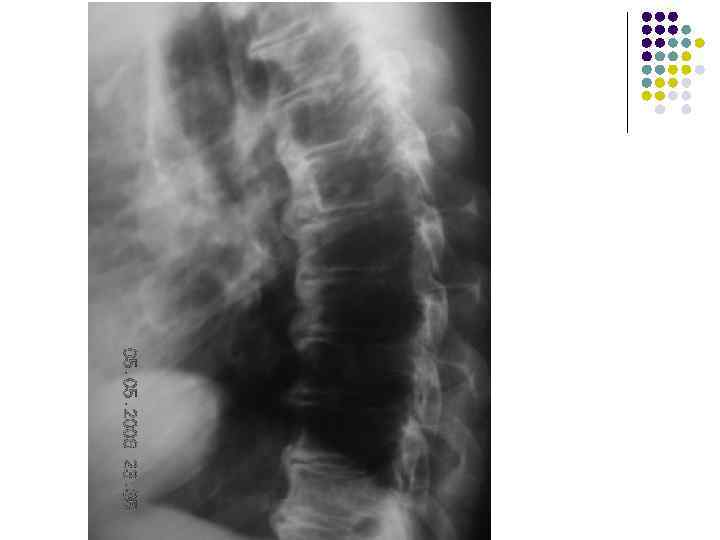

l На рентгенограмме грудного отдела позвоночного столба в боковой проекции определяются признаки выраженных, распространенных дистрофических изменений в виде болезни Форестье за счет характерных костных разрастаний под передней продольной связкой практически во всех визуализированных отделах грудной части позвоночника. На этом фоне отмечаются также явления умеренного и также распространенного отсеохондроза – сужение межпозвонковых простанств, субхондральный остеосклероз, соответствующие костные разрастания. Положение тел позвонков правильное, деструктивных изменений нет.